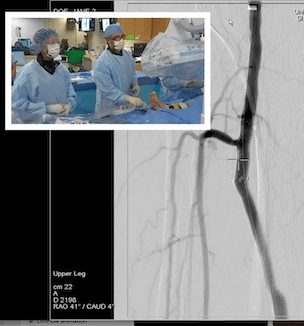

CLEVELAND, Ohio – The U. S. Food and Drug Administration (FDA) today announced approval of a therapy giving thousands of patients hope for an alternative to amputation of their legs. LimFlow therapy is a novel and minimally invasive procedure designed to bypass blockages in arteries of the legs and restore blood flow for many thousands of people suffering from a severe form of vascular disease known as chronic limb-threatening ischemia (CLTI).

LimFlow takes a new approach to treating patients who are facing major amputation because they have no other suitable treatment options, such as traditional bypass surgery or endovascular revascularization, due to extensive disease in the target arteries or other anatomical constraints. Using proprietary devices, the procedure essentially turns a vein, which returns blood to the heart, into an artery, which carries oxygen-rich blood from the heart throughout the body. This shift rushes blood back into the foot.